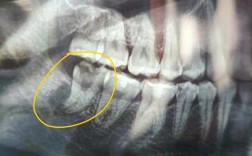

部分患者为追求“快速矫正”,要求医生加大矫治力,或医生未严格遵循“缓慢移动”原则(如每月移动距离超过1mm),可能超出牙槽骨改建的承受能力,导致牙齿“被动松动”,甚至引发牙根吸收(X光片可见牙根变短)。 -

- X光片显示牙根吸收(牙根长度缩短>1/3);

- 若已出现牙根吸收,需定期拍摄X光片监测,若吸收进展迅速,可能终止正畸或更换矫正方式(如隐形矫正的轻力系统)。